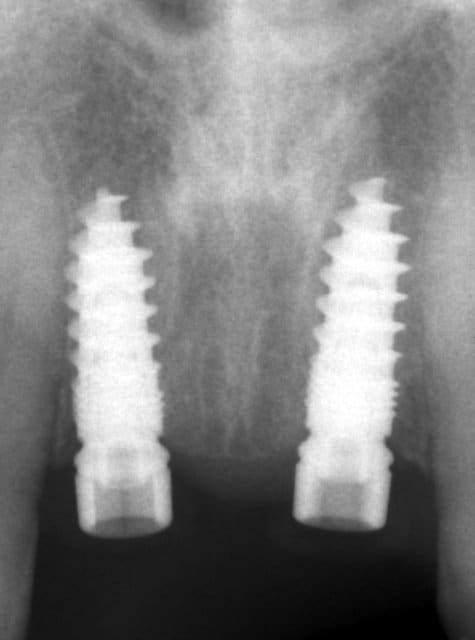

> Sinon, c'est normal d'avoir plusieurs spires à nu sur l'implant remplaçant la 11

pas d'inquiétude pour la petite fente osseuse laissant apparaître un peu les spires.

le plus important, c'est la position des implants.

> pas d'inquiétude pour la petite fente osseuse laissant apparaître un peu les spires.

Pas trop d'accord..ça peut jouer sur le résultat final (esthétique)

> pas d'inquiétude pour la petite fente osseuse laissant apparaître un peu les

> spires.

> le plus important, c'est la position des implants.

tu veux dire qu'on s'en fou complètement d'avoir des spires a nu?

et quel avenir pour cette corticale toute fine?

> > pas d'inquiétude pour la petite fente osseuse laissant apparaître un peu les

> > spires.

> > le plus important, c'est la position des implants.

> tu veux dire qu'on s'en fou complètement d'avoir des spires a nu?

>

non, bien entendu ce serait mal me connaitre. il y a eu une ROG aussi.

Une petite RX serait la bienvenue